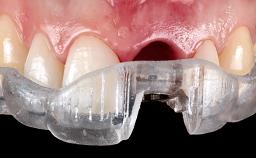

Open-Flap Debridement for the Management of Peri-Implant Mucositis Associated with Excess Cement

A 79-year-old female patient was referred to the Department of Periodontology of the University of Bern, Switzerland by her private dentist in May 2019. She had been rehabilitated in May 2005 with two tissue-level implants (Institut Straumann AG, Basel Switzerland) at sites 13 and 15, supporting a three-unit cemented fixed dental prosthesis (FDP). The metal-ceramic FDP had been cemented permanently with a glass-ionomer cement (Ketac Cem; 3M ESPE, Seefeld, Germany). Implant 13 had been diagnosed with peri-implant mucositis by the referring dentist in the course of regular supportive therapy. The patient was in good general health, did not smoke, and exhibited good self-performed plaque control.